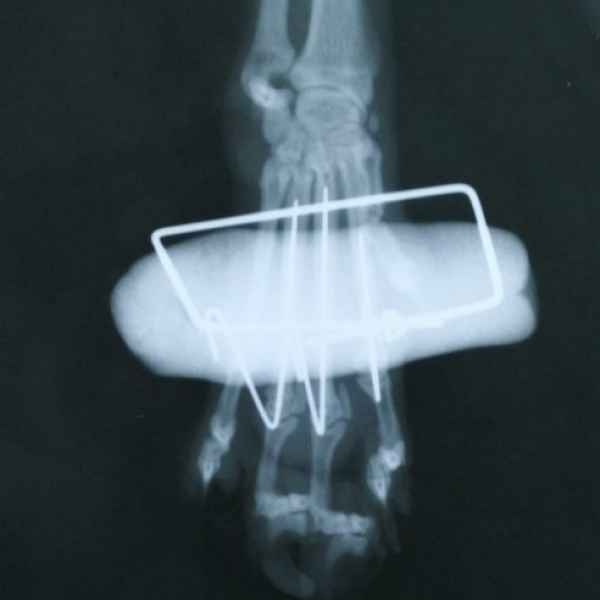

Этот пациент поступил к нам с кусаной раной левой грудной конечности После рентгенологического исследования обнаружили перелом костей предплечья. Сложность операции заключалось в том, что дистальный отросток лучевой кости был очень коротким. Хирургом нашей клиники было принято решение установить блокируемую lcp пластину. В данный момент пациент полностью восстановился..